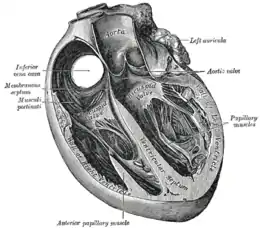

Base of ventricles exposed by removal of the atria. (Bicuspid (mitral) valve visible at bottom left.

Tricuspid valve visible at bottom right.) | |

The human heart, viewed from the front. The mitral valve is visible on the right as the "bicuspid valve"

The human heart, viewed from the front. The mitral valve is visible on the right as the "bicuspid valve"